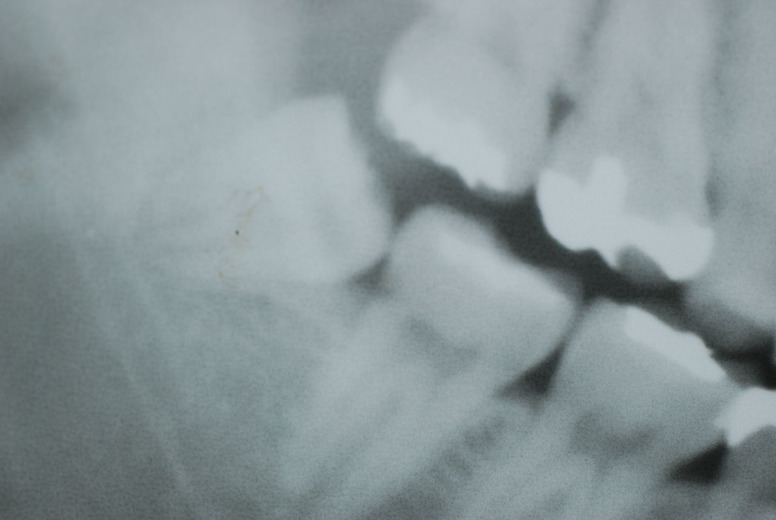

レントゲンでは小さいですが、こう言う虫歯が一番怖いのです。

隣の14歳大臼歯がひどい虫歯になり治療不可能になりつつある状態のレントゲン